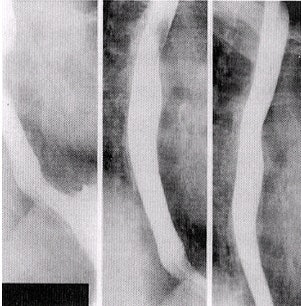

| PA oblique esophagus, RAO position (the midsagittal position forms an angle of 35°-45° from the grid device). Image courtesy of Dr. Naveed Ahmad. |

| PA oblique distal esophagus, RAO position, double-contrast spot image. Image courtesy of Dr. Naveed Ahmad. |

- Image the entire esophagus as the patient is drinking, observe the esophagus for a "silver-satin" appearance -- indicating the best possible coating -- and obtain images of the proximal esophagus, midesophagus, and the distal esophagus.

- The right anterior oblique (RAO) position is usually used in preference to the left anterior oblique (LAO) position. An RAO position of 35°-40° gives a wider space for an image of the esophagus between the vertebrae and the heart. The LPO position may also be recommended.